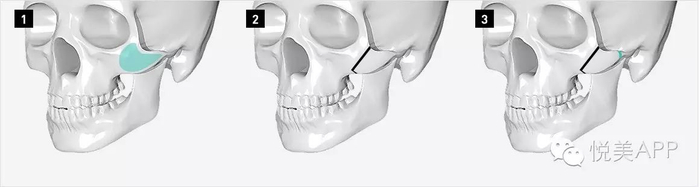

[ 固定 ]

颧骨手术必须固定,前后都用钛板钛钉固定!

固定 VS 咬肌牵拉

咬肌上端附着于颧骨颧弓的下方和后方,下端附着于下颌角,下颌升支。承担主要的咀嚼功能。

长期的进食咀嚼,咬肌的收缩对颧弓颧骨下方施加持续的张力,是造成颧弓颧骨手术后颧弓骨块下移的主要因素。

目前,在韩国和我国的一些医生理念中:颧弓两端离断,前方需要固定,后方不需要固定。后方靠骨组织周围的骨膜和韧带悬挂,不至于下移。

但咬肌的强大力量长期牵引,仍然造成了以下案例后端骨端的下滑,同时对前方的颧骨固定点形成了杠杆作用,强大的杠杆力使得前方固定点上端裂开。最终使颧弓向后下方旋转,翻转。

以下案例,后端未固定,只把整段骨块内移插入到后方骨端的内侧,但由于术后患者的咬肌运动,牵拉骨块,使得后段本来重叠推进去的骨端弹出,所以面部宽度最终未能缩小。

所以,颧骨两端固定是完全必要的。

而且固定需用钛板钛钉,韩国一些医院医生选择用价格低廉的铁丝等,容易引发骨不连、骨块下移和疼痛(有整友诉说自己铁丝固定,面部疼痛)。

骨不连,骨块下移

颧弓根部的截骨少量内推时,内推范围不超过颧弓根截面,要能接上才能骨性愈合。推多了后端骨头连不上,仅靠钛板固定,在咬肌牵拉下,单靠钛板钛钉固定仍然容易骨不连、下移、弹出。

后端的牵拉对前端造成杠杆效应,使得前方固定点上端裂开,最终使颧弓向后下方旋转,翻转。导致骨不连,骨块下移。